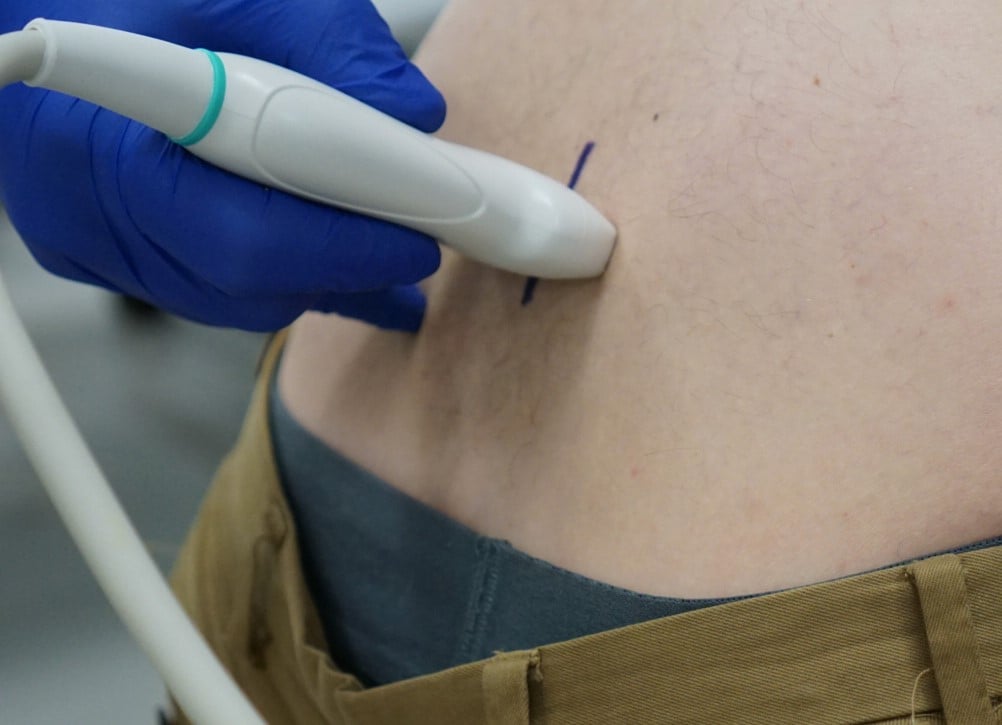

One recommended approach is to start with the probe in transverse position at the level of the sacrum and scan superiorly, sequentially identifying the spinous processes of L5, L4, L3, and L2. In the transverse orientation, spinous processes are seen as small, hyperechoic marks with dense vertical shadowing (Figure 1). With the probe centered over a spinous process, the operator uses a clean towel to wipe off excess gel, and a skin marker to place a vertical hash mark above and below the midline of the probe (Figure 2). Next, the probe is placed in longitudinal orientation over the same spinous processes, with the indicator toward the patient’s head. In this view, spinous processes will appear as wider, hyperechoic areas with distal shadowing (Figure 3). When two or more spinous processes are simultaneously visualized, the space between them is the area available for needle insertion. The skin is marked again, this time with horizontal hash marks extending outward from the midline of the probe (Figure 4).

Figure 2. Ultrasound transducer in transverse plane with midline hash marks